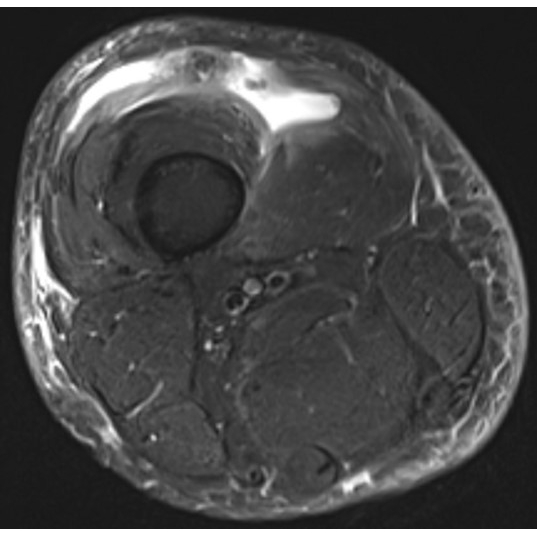

| Knee Pain After Escaping A Dog - Page #3 | |||